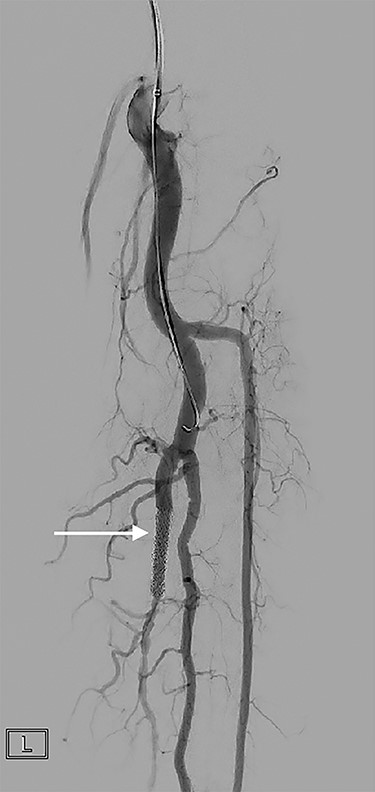

Formal angiogram was undertaken and posterior tibial AVF was confirmed (Fig. 1). Two Advanta V12 polytetrafluoroethylene covered balloon-expandable stents were placed in the posterior tibial artery (Merrimack, NH, USA): 5 × 22 mm distally and 6 × 22 mm proximally, resulting in successful exclusion of the fistula (Fig. 2).

Focused angiography pre-intervention with a catheter positioned at the origin of the tibio-peroneal trunk (TPT). Contrast flows into the TPT, through the AVF (arrow) and into the venous system.